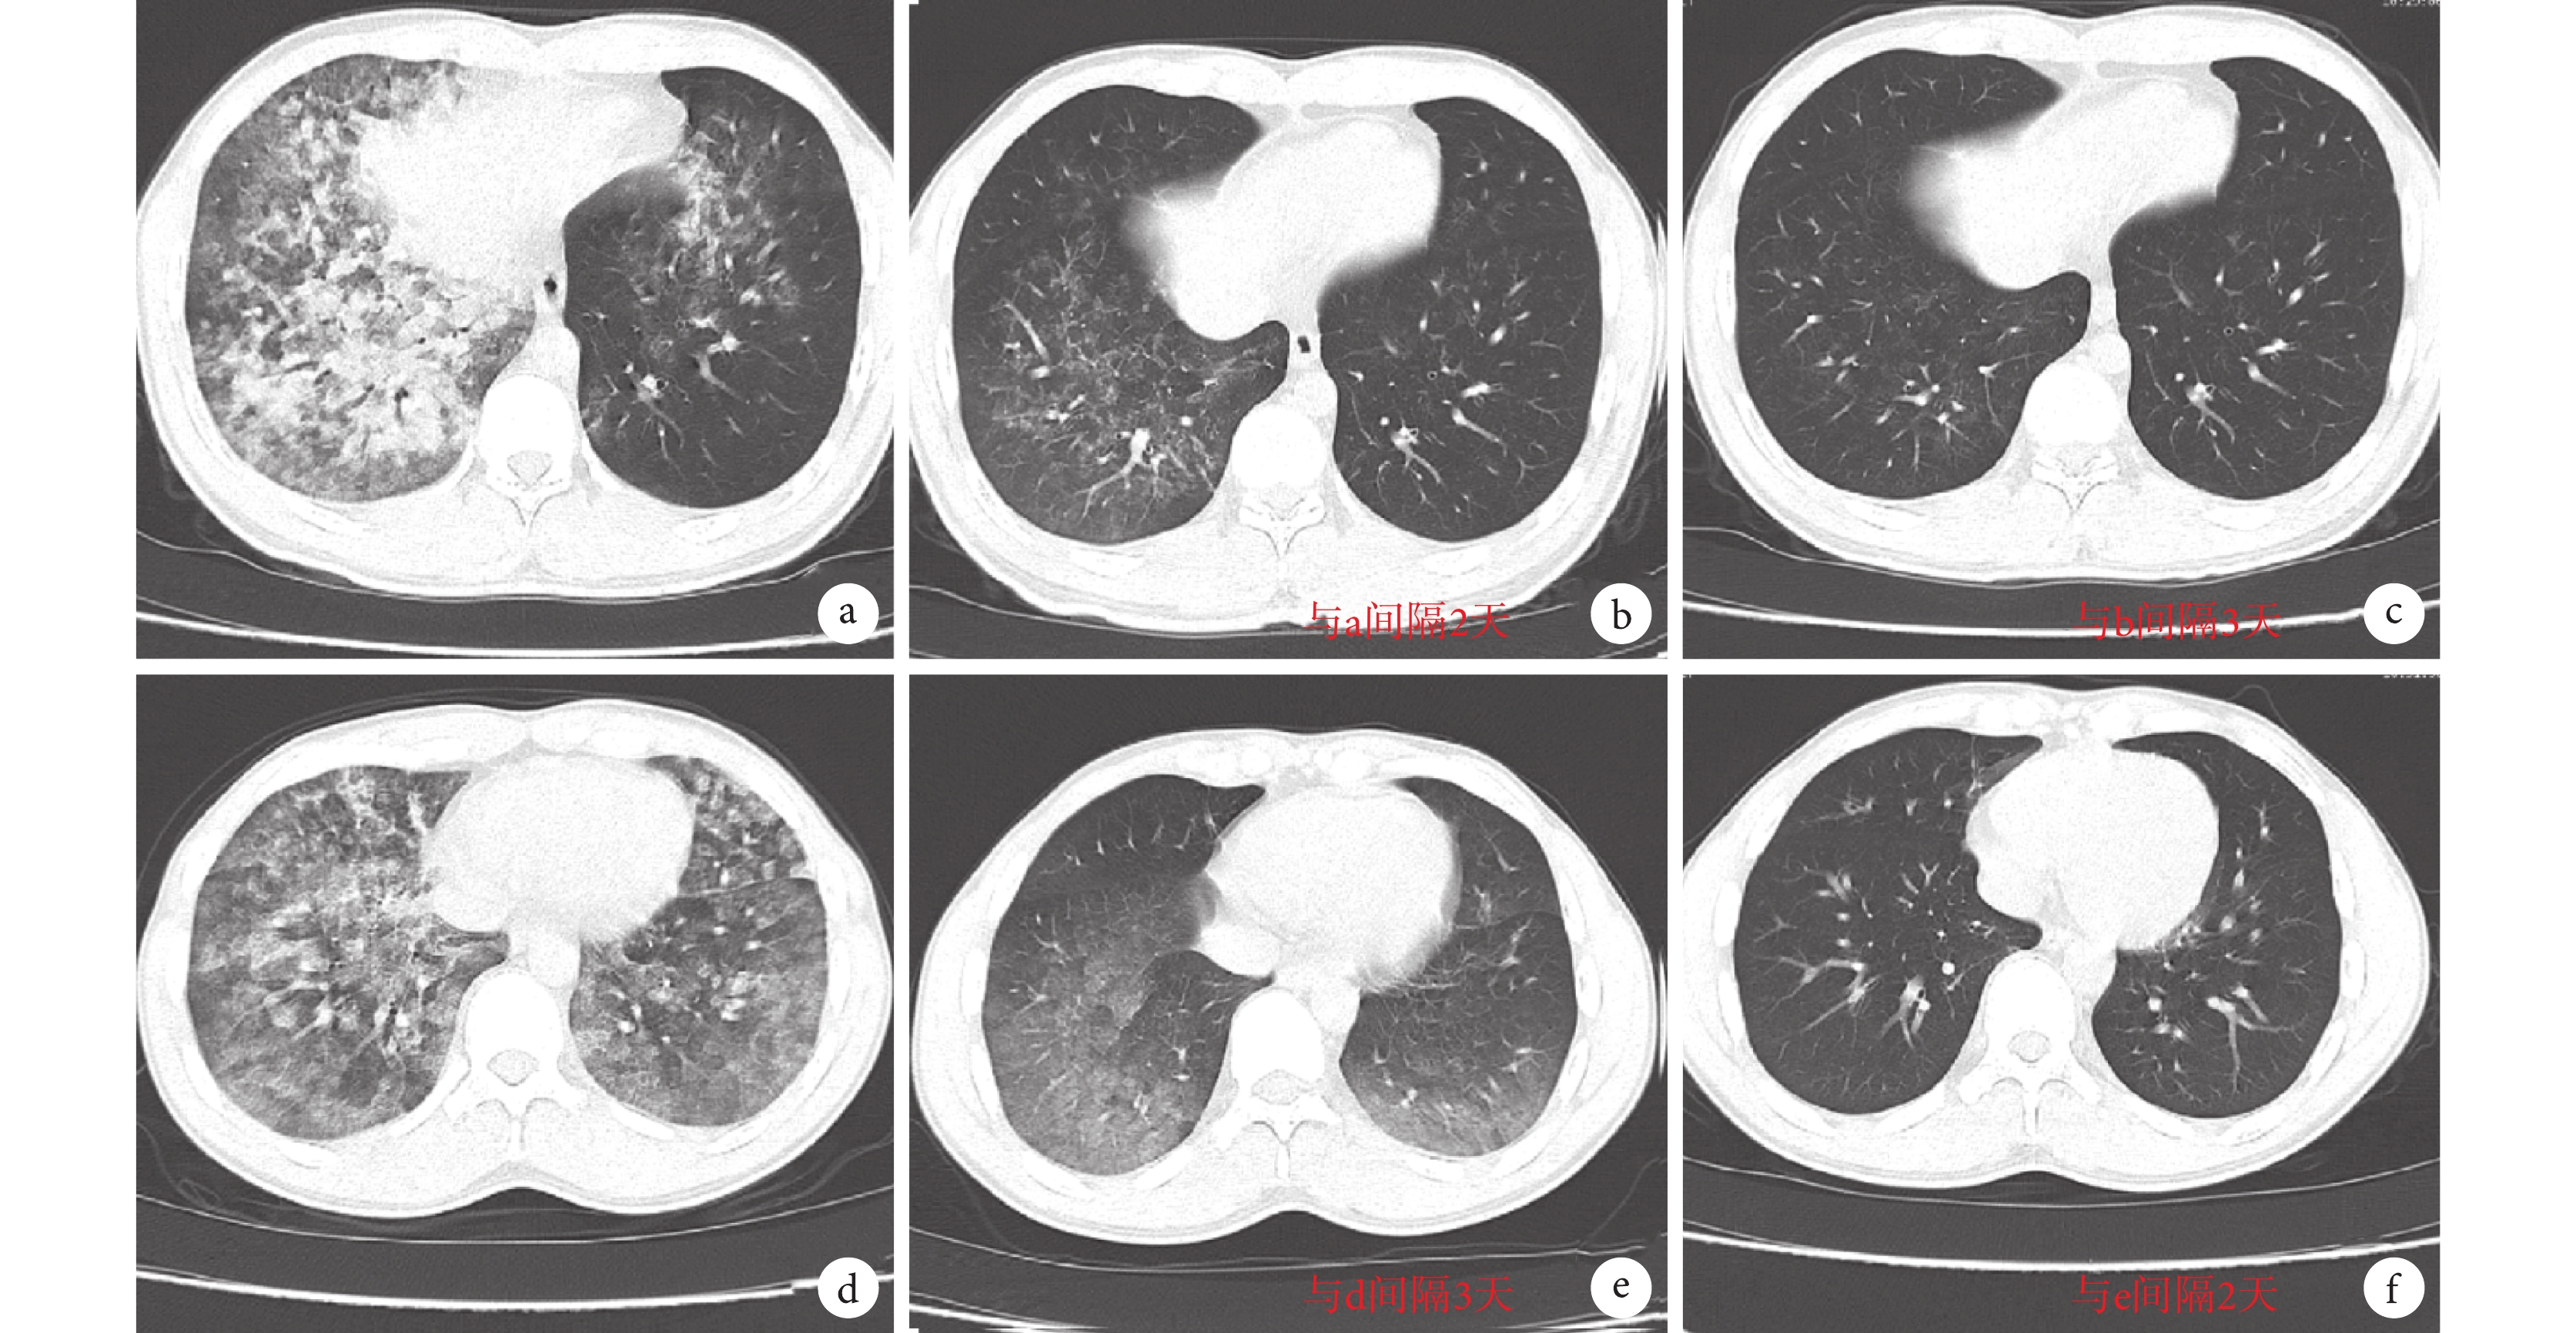

2.2.3 重癥爆發期

此期病變繼續向周圍擴展,絮狀密度增高影可充滿整個肺葉(見圖 3a、圖 3d),部分可見受累肺段的支氣管充氣征,右肺受累程度多重于左肺。

a. 患者 1 重癥爆發期;b-c. 患者 1 轉歸吸收期;d. 患者 2 重癥爆發期;e-f. 患者 2 轉歸吸收期

Figure3. CT images of HAPE in the most serious and last stage of two patientsa. the most serious stage of patient No.1; b-c. recovery period of patient No.1; d. the most serious stage of patient No.2; e-f. recovery period of patient No.2

2.2.4 轉歸吸收期

此期病變 CT 表現與早期表現類似(見圖 3b、c 和圖 3e、f),表現為肺紋理略增多,顯示模糊密度影或局限性小斑片陰影,經過治療后可完全吸收。